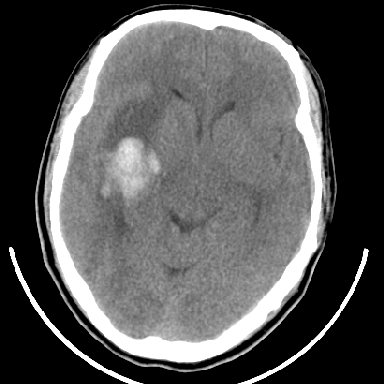

标题: CT6056:脑出血(血管畸形?)

m 40突发头痛左侧偏瘫3小时

考虑高血压性脑出血,依据:

1是高血压性脑出血的好发部位,形态呈肾形,是高血压性脑出血的常见形状

2增强时占位效应加重了,考虑出血还没有停止

3病灶周围水肿不是太厉害,一般肿瘤出血水肿多非常明显

4病灶周围的‘软组织’影没有明显的强化

5至于脑血管畸形引起的出血,暂时没有看到明显的畸形血管影,也不太支持

支持右侧基底节脑出血

右侧基底节区脑出血.

支持右侧基底节区(主要为外囊区)原发性脑出血。

另附部分资料:“血液溢出血管外形成血肿,其内含有大量血红蛋白、血浆白蛋白,球蛋白,因这些蛋白对x线的吸收系数高于脑质,故ct呈现高密度阴影,ct值达40~90h,最初高密度灶呈非均匀一致性,中心密度更高,新鲜出血灶边缘不清。基底节区血肿多为“肾”型,内侧凹陷,外侧膨隆,因外侧裂阻力较小,故向外凸,其它部位血肿多呈尖圆形或不规则形”

术中抽出40ml陈旧血液,血肿底部似见一条索血管影